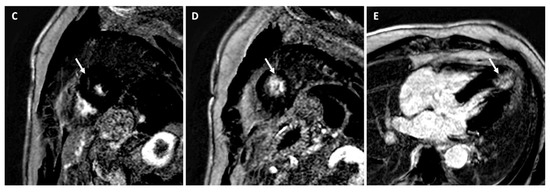

Arrhythmogenic Right Ventricular Cardiomyopathy

Left Dominant Arrhythmogenic Cardiomyopathy (LDAC)

- Palumbo, P.; Cannizzaro, E.; Di Cesare, A.; Bruno, F.; Schicchi, N.; Giovagnoni, A.; Splendiani, A.; Barile, A.; Masciocchi, C.; Di Cesare, E. Cardiac magnetic resonance in arrhythmogenic cardiomyopathies. Radiol. Med. 2020, 125, 1087–1101. [Google Scholar] [CrossRef]

- Miles, C.; Finocchiaro, G.; Papadakis, M.; Gray, B.; Westaby, J.; Ensam, B.; Basu, J.; Parry-Williams, G.; Papatheodorou, E.; Paterson, C.; et al. Sudden Death and Left Ventricular Involvement in Arrhythmogenic Cardiomyopathy. Circulation 2019, 139, 1786–1797. [Google Scholar] [CrossRef] [PubMed]